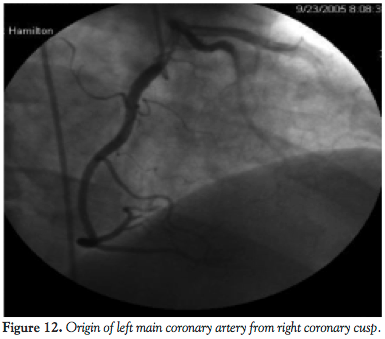

Case report 2. A 46-year-old male had a history of hyperlipidemia, diabetes mellitus, mitral regurgitation, hypertension, and chest pains. His physical examination was unrevealing. Cardiolite stress test revealed apical scar and 2-D echocardiogram revealed an ejection fraction 55% with mild mitral regurgitation. A cardiac catheterization was performed due to persistent chest pains and revealed an anomalous coronary artery where the entire left coronary artery and RCA arose from one origin at the right coronary cusp. No obstructive lesions were noted.

A subsequent CT angiography was obtained to delineate the course of this vessel. A 64-slice CT scan revealed that the left coronary artery coursed in between the aorta and pulmonary artery. In view of his ongoing chest pains, with a high risk of myocardial infarctions (MI), fatal arrhythmias, and sudden death, CABG was recommended.

The second case illustrates the left main coronary artery arising from the RCA and passing in between the aorta and main pulmonary trunk. This anatomy corresponds to the IIB2 classification of the isolated coronary artery anomalies.5 In this case, the risk of MI, fatal arrhythmias, syncope, and sudden death is significantly increased and it is postulated that this may occur as a result of an expansive effect of the aorta during exercise. This leads to the compression of the left coronary artery, which results in chest pains, angina, arrhythmias, and even sudden death. Our patient was found to have had a negative noninvasive work-up for coronary artery disease but in spite of this, had persistent recurrent chest pains for which coronary artery angiography was recommended.